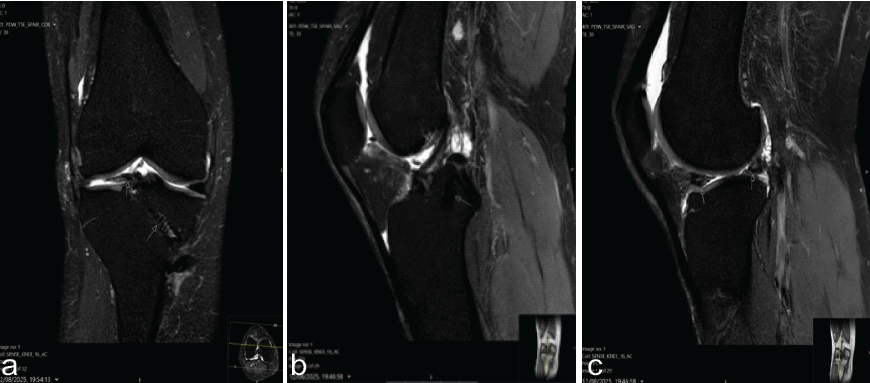

MRI examinations were obtained preoperatively, as well as at 6 and 12 months postoperatively. At the 1-year follow-up, MRI demonstrated correct positioning of the anterior and posterior roots and their corresponding tunnels, with a residual meniscal hypersignal on T2 sequences (Fig. 7).

Figure 7: Magnetic resonance imaging T2 sequences. (a) Coronal section showing the anterior root of the external meniscus graft (left arrow) and the anterior tibial tunnel (right arrow). (b) Sagittal section showing the posterior root of external meniscus graft (upper arrow) and the posterior tibial tunnel (lower arrow). (c) Sagittal section showing the anterior and posterior roots of external meniscus grafts.